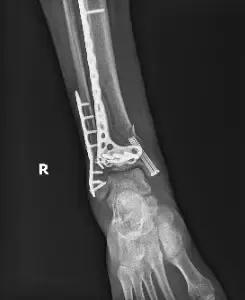

La fractura conminuta de la tibia, que ha sido fijada con pasadores quirúrgicos y puede determinarse en la posición de los instrumentos quirúrgicos, parece satisfactoria. La férula de yeso está en su sitio.

Estado post-ORIF con placa y tornillos en el peroné distal y la tibia con 2 tornillos en la maléola medial. Una parte de la línea de fractura sigue siendo evidente en la tibia.

Las radiografías y la tomografía computarizada confirmaron fracturas en cicatrización con una mortaforte congruente, pero pinzamiento de hardware en dorsiflexión y aversión.

Estado post-ORIF con placa y tornillos en el peroné distal y tibia distal con fractura cicatrizada del miembro distal de la tibia con deformidad leve y alineación anatómica mantenida. Fractura cicatrizada de la fíbula distal sin deformidad residual.

Fractura de la maléola medial cicatrizada sin deformidad.